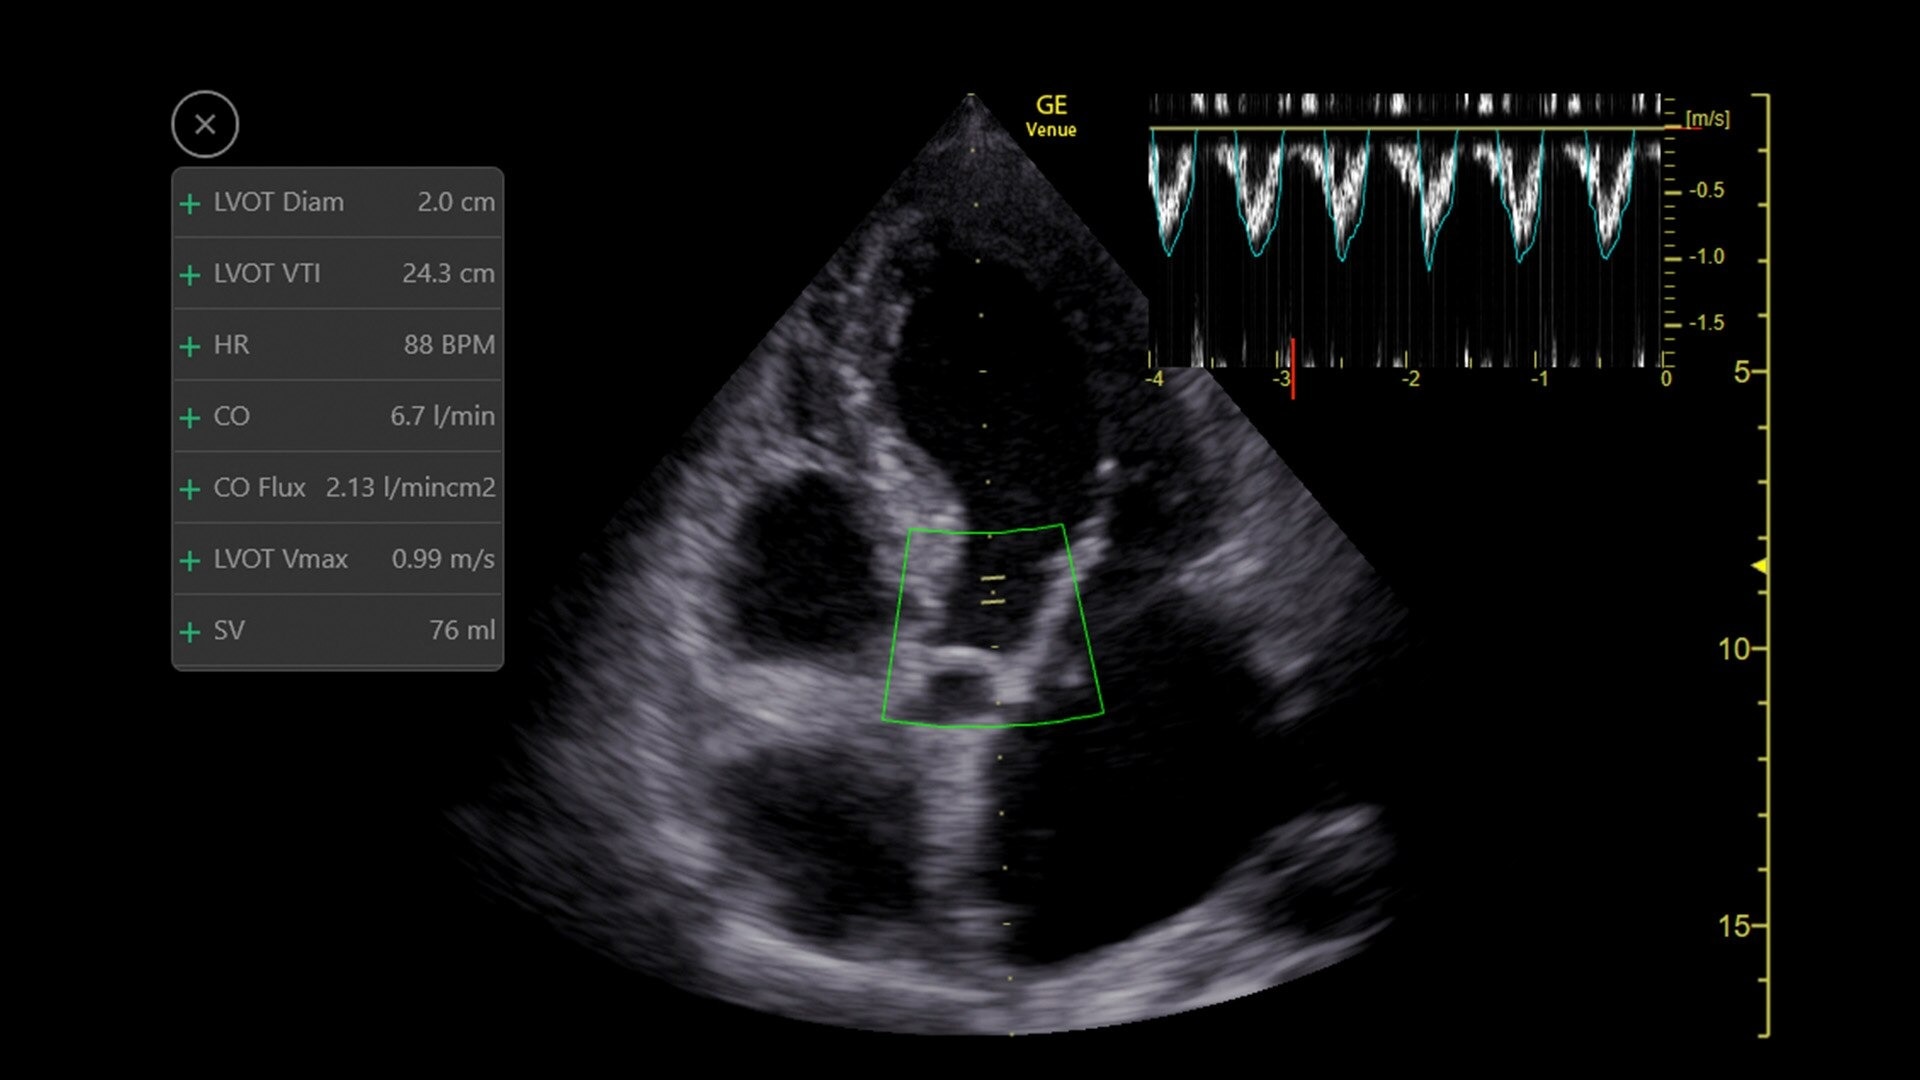

Automated tools

Simplify your workflow with AI-enabled clinical tools.

Helping drive consistency from user to user (whether one is an ultrasound novice or expert), Venue Fit features AI-enabled resources that help clinicians work smarter and more efficiently. Utilizing proprietary algorithms, we synthesize data from numerous patients to ensure accurate calculations for clinical confidence.